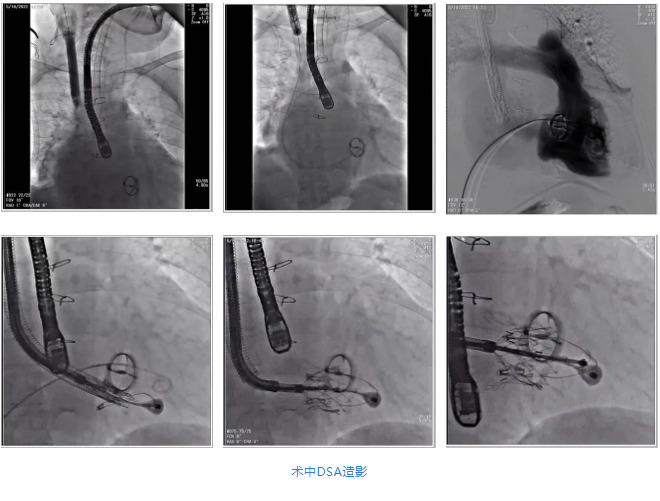

根據術前評估結果,郭應強教授團隊為患者量身定制了手術策略,決定使用LuX-Valve Plus經血管三尖瓣置換系統(tǒng)開展手術治療。手術在全麻下進行,采用經右側頸靜脈入路,在經食道超聲和DSA的指引下調整輸送器角度以達到正確位置,勾住前瓣后逐步釋放盤片,盤片打開后順利扎針,最終完成瓣膜植入,輸送器撤出。術后超聲提示人工三尖瓣同軸性良好,瓣架固定牢靠,無反流和瓣周漏,術后三尖瓣平均跨瓣壓差為1 mmHg。